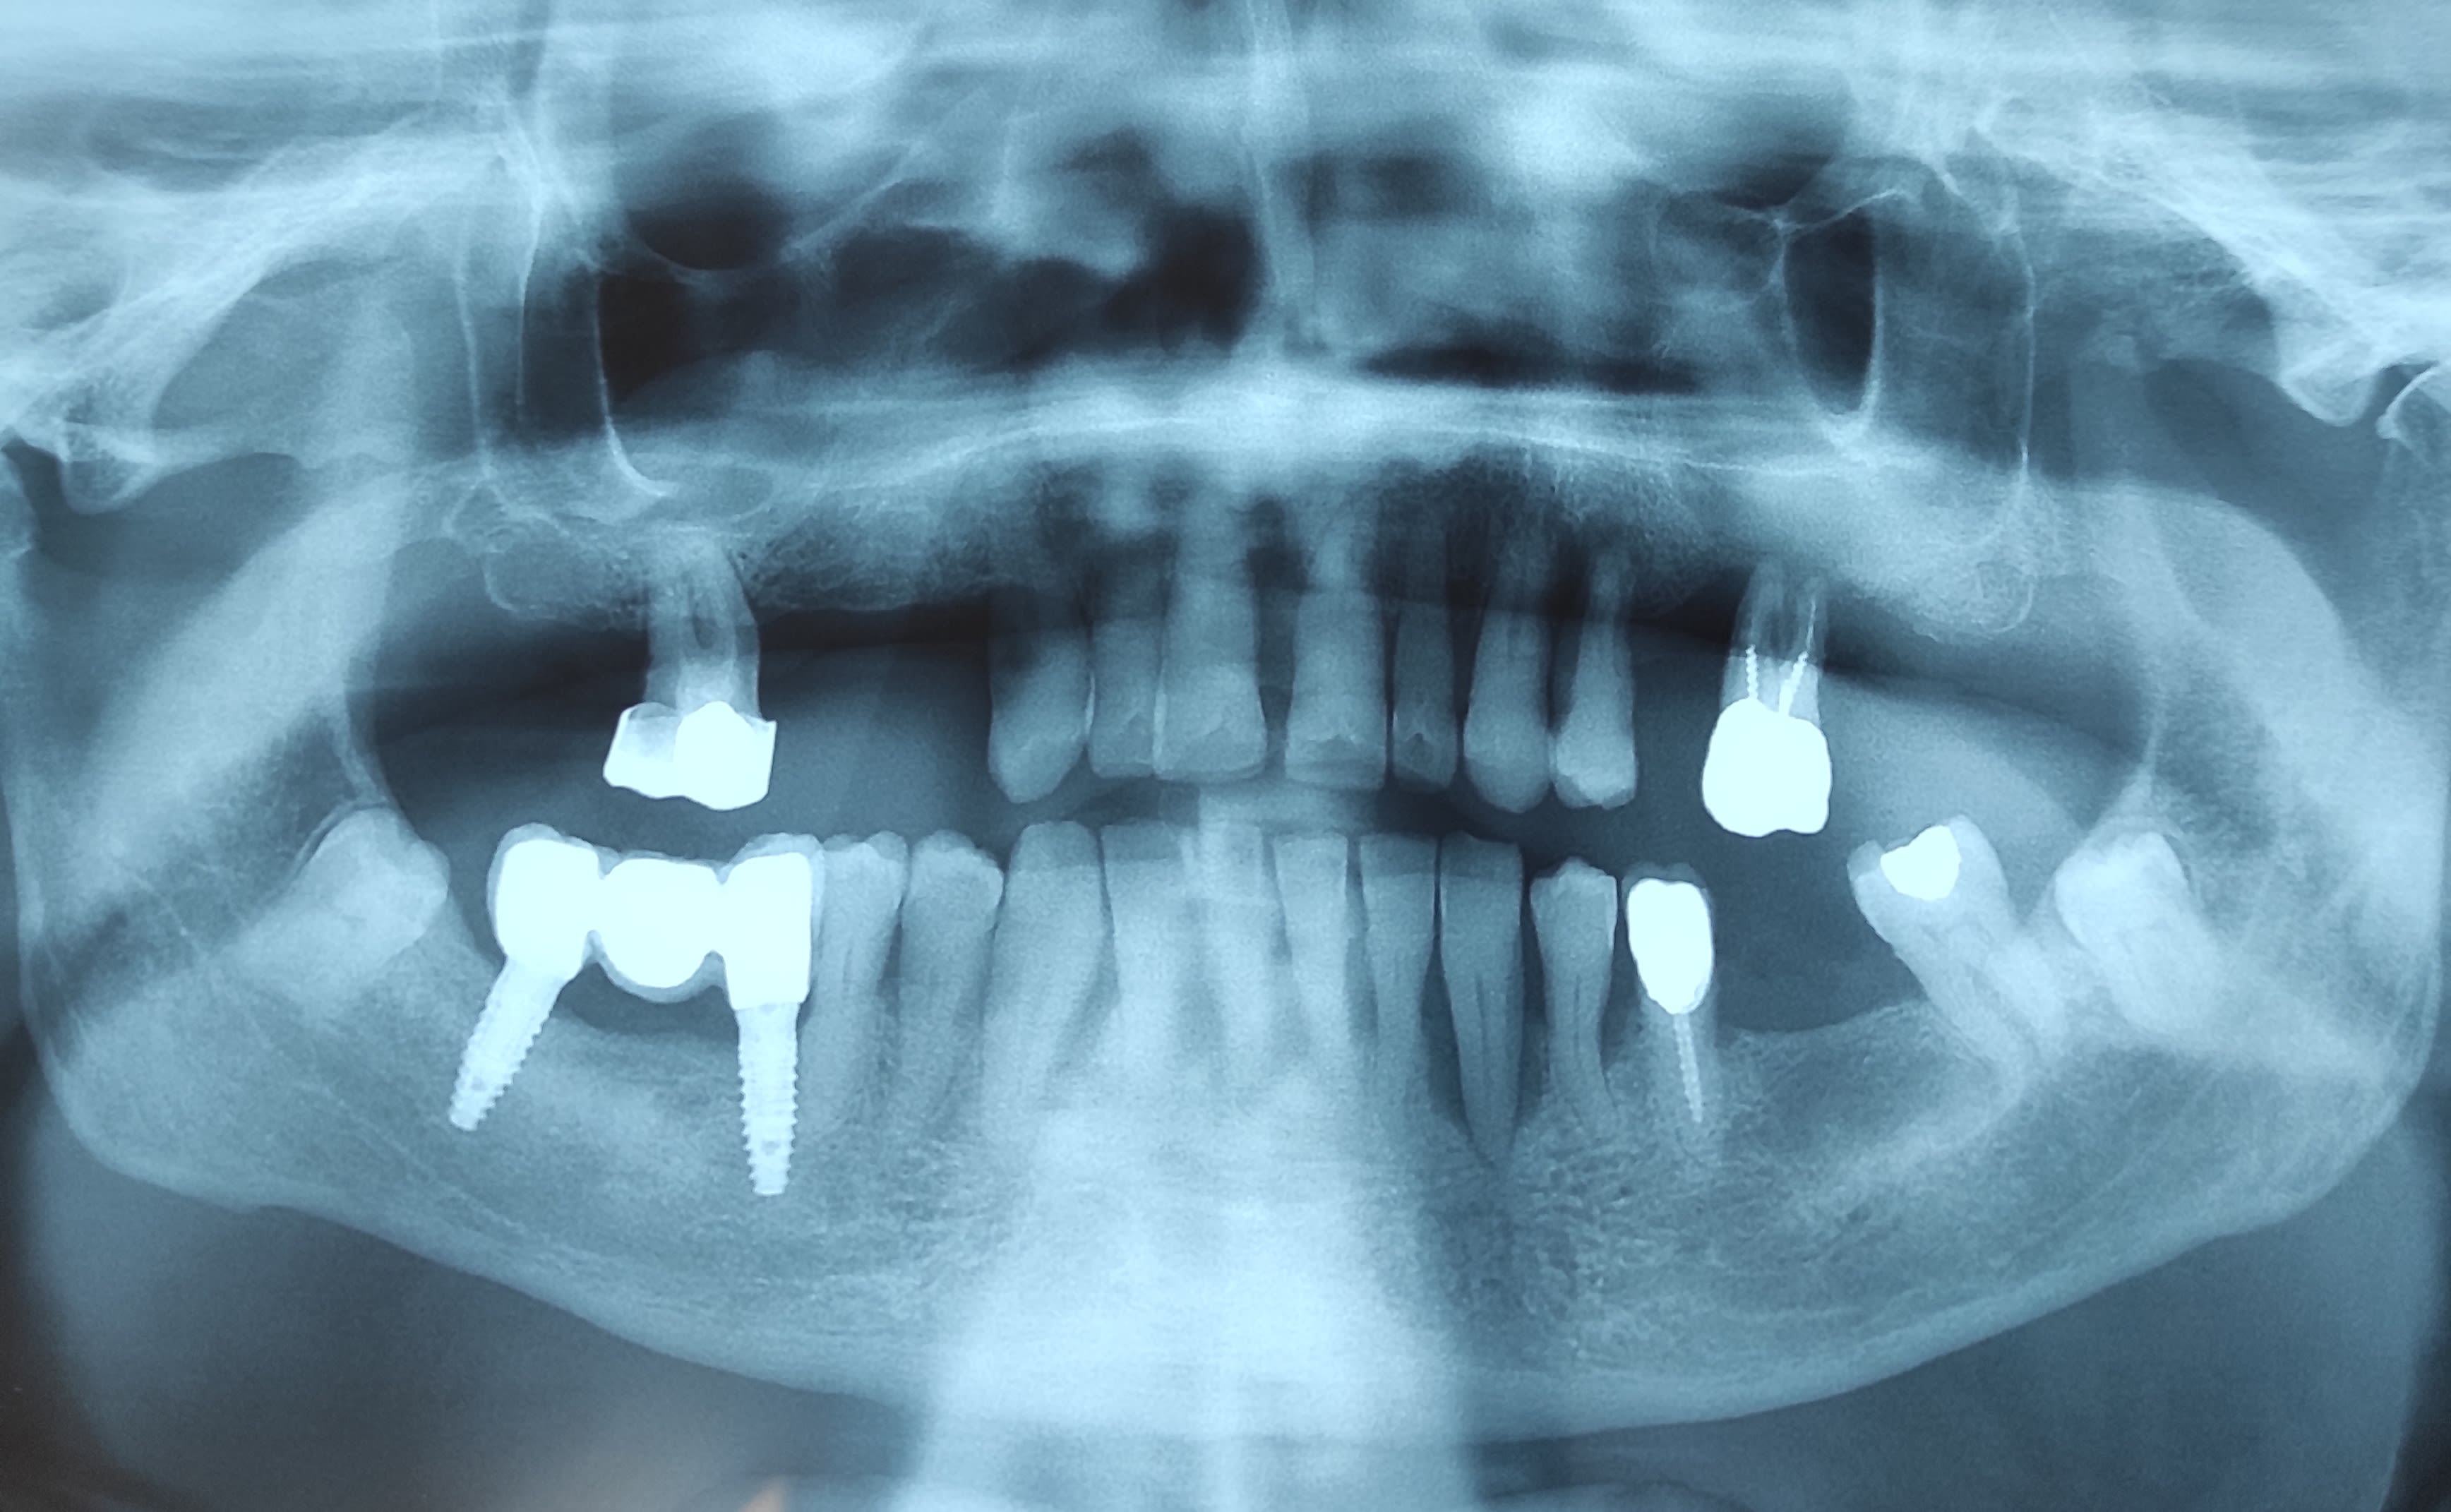

Bin j'ai récupéré ce cas. Il y a de l'ancien et du contemporain. Le dernier acte est ce splendide bridge sur implants, moins de deux ans, réalisé par "un jeune dentiste très bien qui m'a pris en urgence au mois d'août pendant mes vacances."

Au moins je sais que j'ai affaire à une parodontite très agressive, puisqu'elle n'existait pas il y a deux ans 😁.

(il a bien visé pour l'implant distal, vu la distance avec le NDI)

L'implant mésial ne serait pas intradentaire par hasard ?

c est de la stabilisation par appui radiculaire

Ou une résection apicale.